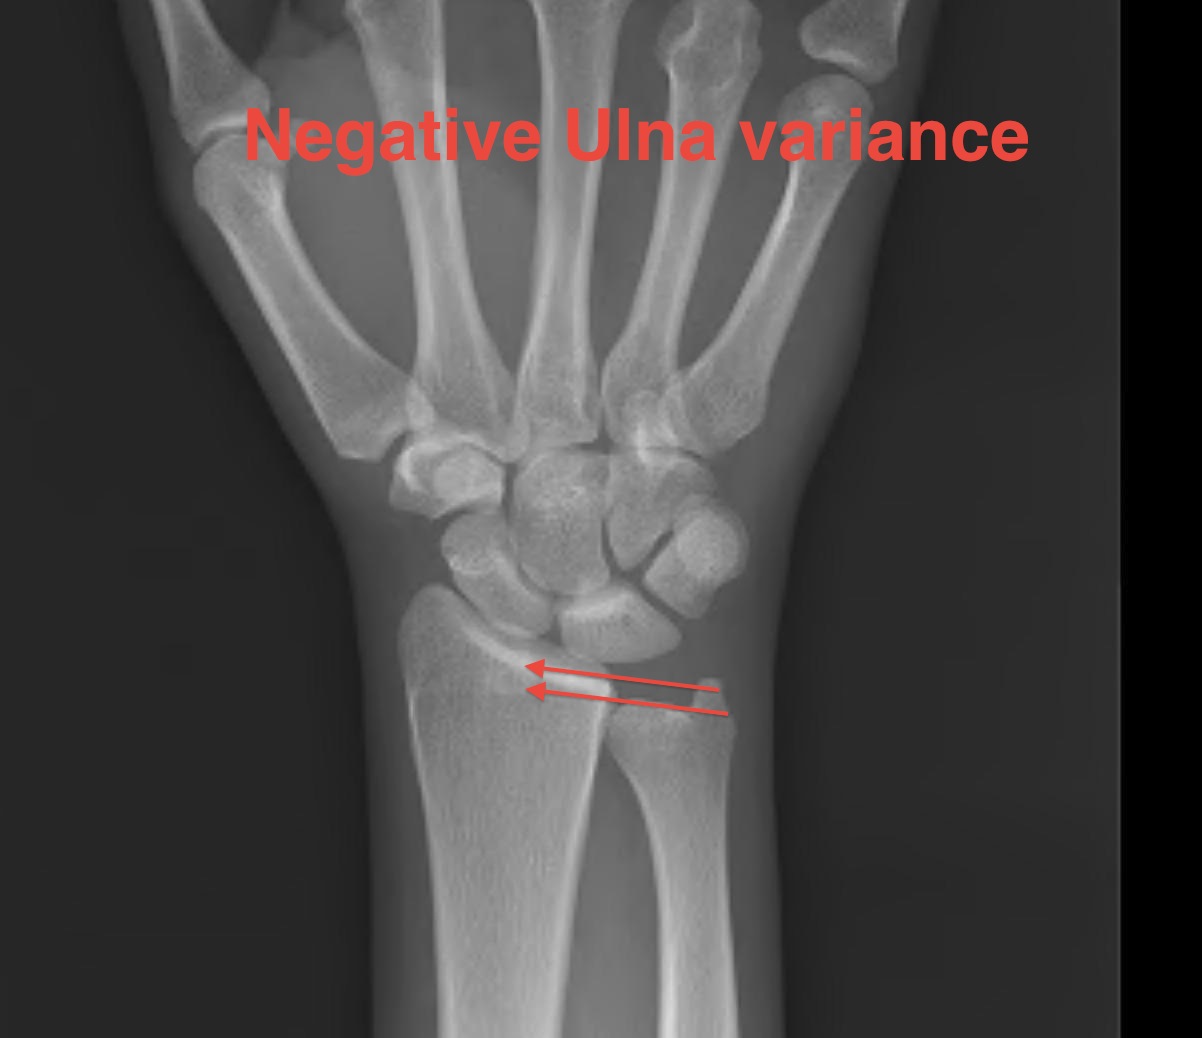

Mechanical theory: ulna minus variance causes increased radioulnar load on lunate

ulna neg

Ulna Variance

Supination and pronation alter variance

90 / 90 view (elbow 90° / shoulder abducted 90°)

- neutral supination / pronation

- PA film with wrist in neutral

- line from lunate fossa and ulna head

ulnaulna

Ulna neutral

Ulna positive

ulna negulna

Ulna negative

Radial shortening - ulna negative

Indication

Stage II / IIIA

Negative ulna variance

Theory

Radius normally takes 80% of load

- with ulnar minus is increased to 96%

- 2mm radial shortening: 20% decrease radiolunate load

- 4mm radial shortening: 40% decrease in radiolunate load